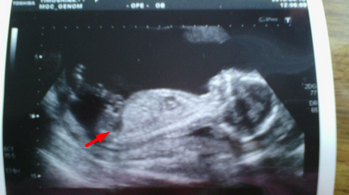

Девочки с опытом, подскажите, пожалуйста, видно ли на снимке, что это мальчик?

я даже полового бугорка не вижу, ножки сильно согнуты. А почему вам с другого ракурса не посмотрели (со стороны попы)?

мне ребенка с другого ракурса смотрели чтобы увидеть гениталии, мне кажется, в таком разрезе не смотрят